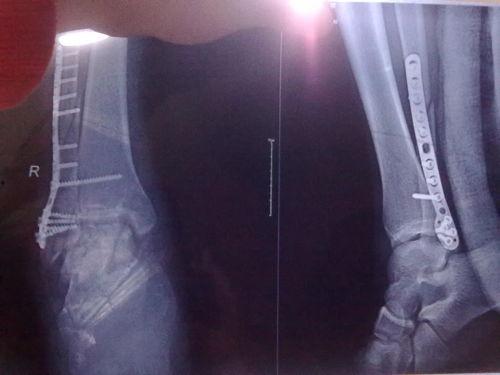

三、脚踝韧带撕裂的图片展示

下面是一些真实的脚踝韧带撕裂图片,让你直观地了解这种损伤。

1. 诊断:医生会根据你的症状和体征进行诊断,必要时还会进行X光或MRI检查。